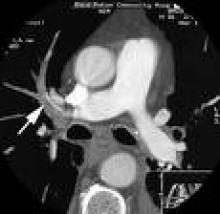

February 25, 2009 - Millard Fillmore Gates Circle Hospital in Buffalo, NY, is reportedly the first U.S. stroke center to offer dynamic volume CT in an effort to reduce diagnosis time for stroke.

Millard recently installed Toshiba’s Aquilion ONE dynamic volume CT system at the hospital’s Kaleida Health Stroke Center.

February 25, 2009 – The Kaleida Health Stroke Center at Millard Fillmore Gates Circle Hospital in Buffalo, N.Y. has installed Toshiba’s Aquilion ONE dynamic volume CT system, making it the first U.S. stroke center to offer dynamic volume CT to dramatically reduce stroke diagnosis time.